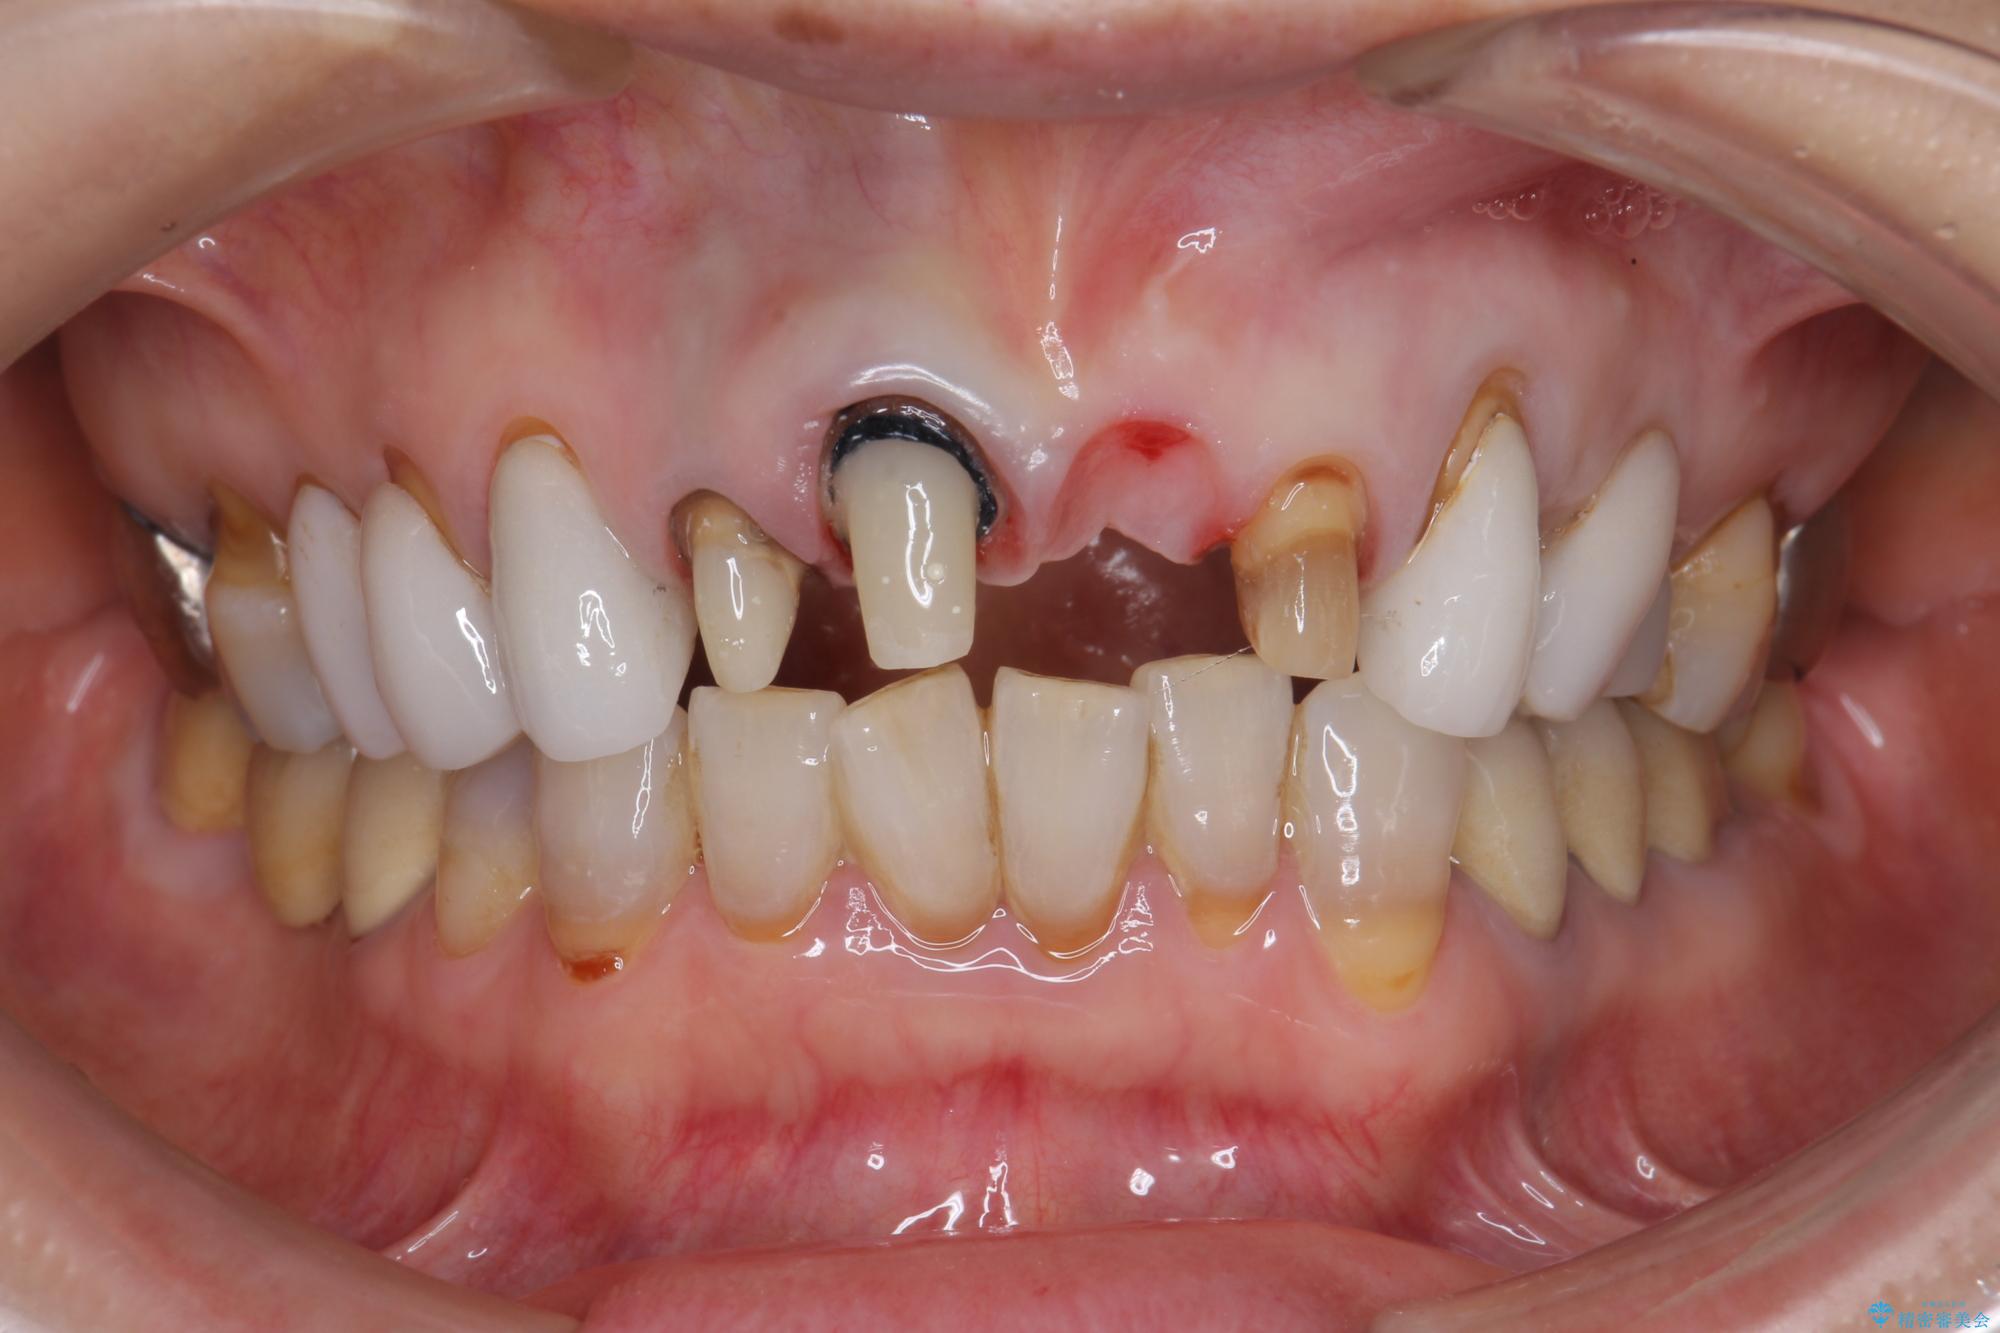

[ セラミック治療 ] 歯ぐきの際の黒ずみを改善したい

- 歯ぐきとセラミックの間の黒ずみが目立つので、きれいに治してほしい。と希望され来院されました。

歯ぐきの位置が変化しクラウン下の歯が見えるようになってしまったことで、審美障害が生じている状態です。

クラウンマージンの再設定を行うことで、黒ずんだ部分を再度覆い、審美障害を改善します。

歯ぐきの位置の経年的な変化は、誰にでも起きうる変化です。

強いブラッシングや電動歯ブラシの当て過ぎなども原因の一因となることがあります。